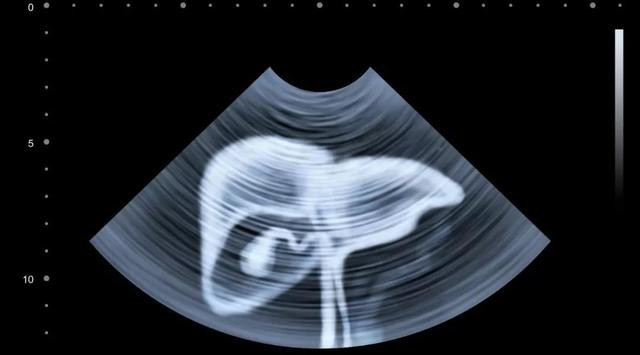

Nếu bạn thuộc 3 nhóm người đầu tiên (viêm gan B, xơ gan, có người nhà là bệnh nhân ung thư gan): Nên xét nghiệm siêu âm B bụng + alpha-fetoprotein huyết thanh (AFP) mỗi 6 tháng;